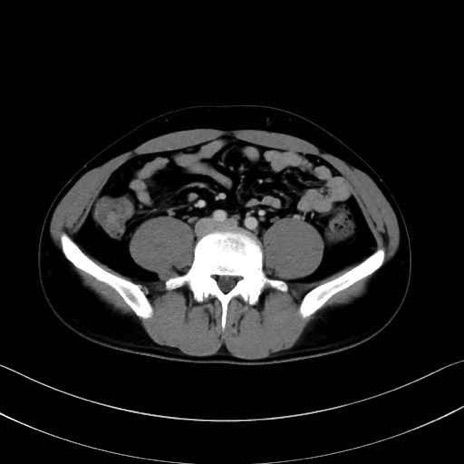

腰方形筋 (Quadratus lumborum)

大腰筋 (Psoas major)